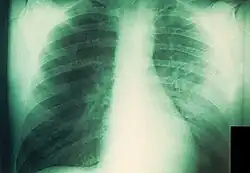

Radiografía de tórax de un enfermo de peste neumónica

La peste neumónica tiene dos formas, primaria y secundaria, frecuentemente mortales y potencialmente contagiosas para los contactos cercanos.[48][49]​ Es más común la secundaria, causada por la diseminación hematógena de la bacteria desde el bubón u otra fuente. Aproximadamente el 10 % de los enfermos de peste en los Estados Unidos desarrollan peste neumónica secundaria, habitualmente por el retraso en el tratamiento de la forma bubónica. Comienza como un proceso intersticial con tos productiva y esputo escaso, que normalmente comienza cinco o seis días después de los primeros síntomas. La radiografía de tórax revela infiltrados alveolares difusos casi siempre bilaterales y acompañados de derrame pleural.[50]​ Sin tratamiento, el esputo se vuelve más copioso y, finalmente, sanguinolento; la muerte ocurre frecuentemente a los tres o cuatro días.[4]

La forma primaria de la peste neumónica es un cuadro fulminante que resulta de la inhalación directa de la bacteria en los pulmones. Puede ocurrir al haber estado en contacto con otra persona con peste neumónica, exposición a animales con peste respiratoria o faríngea (especialmente gatos), infección en el laboratorio o, potencialmente, consecuencia de la liberación intencional de aerosoles con propósitos terroristas. Los síntomas comienzan entre uno y cuatro días después de la exposición; se instauran velozmente e incluyen fiebre, escalofríos, cefalea, malestar, signos generales de endotoxemia, taquipnea, disnea, hipoxia, dolor torácico, tos y hemoptisis. La radiografía de tórax muestra al principio una neumonía lobar que evoluciona a una consolidación densa y diseminación broncopulmonar a otros lóbulos del pulmón ipsilateral o contralateral.[36][51]​ Normalmente, el esputo es purulento, aunque también puede ser acuoso, espumoso y copioso; asimismo, es posible que presente algo de sangre o que sea francamente hemorrágico, en cuyo caso podría contener grandes cantidades de bacilos.[48]​ En cuanto a la histología, el espacio alveolar se muestra lleno de bacterias y células inflamatorias.[43]​ La enfermedad casi siempre es letal sin tratamiento y la mortalidad es también alta cuando este se demora más de 24 horas tras el comienzo de los síntomas. Más o menos, el 25 % de los afectados por peste neumónica en los Estados Unidos desde 1950 han fallecido.[4]